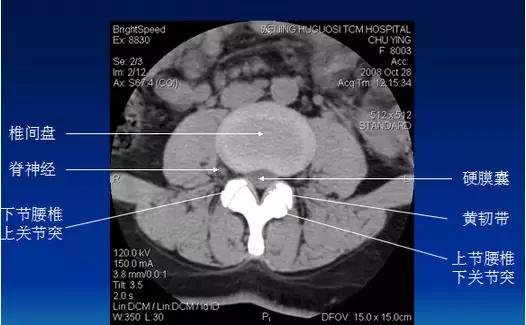

常规腰椎CT扫描L3-S1段,分为

(1)椎体层面(骨窗):观察椎体、附件骨质。

(2)椎间盘层面(软组织窗):观察椎间盘、硬膜囊、神经根、韧带等软组织。